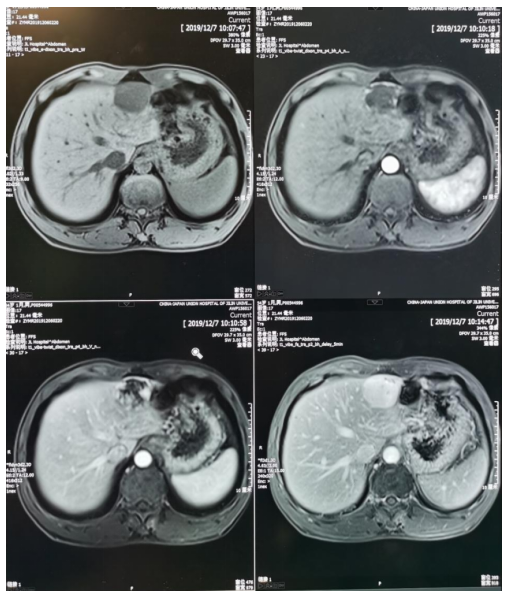

肝脏血管瘤

磁共振胰胆管水成像(MRCP)

胆总管结石(MRCP)

前列腺增生

膀胱癌